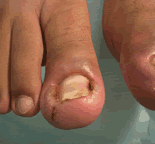

Onicocriptosis Distal Lateral

Tercer grado

Onicocriptosis Tercer Grado Onicocriptosis Distal Tercer Grado onicocriptosis tercer grado Uñas Involutas

Onicocriptosis Distal

Propiamente Dicha

Onicocriptosis Tercer Grado